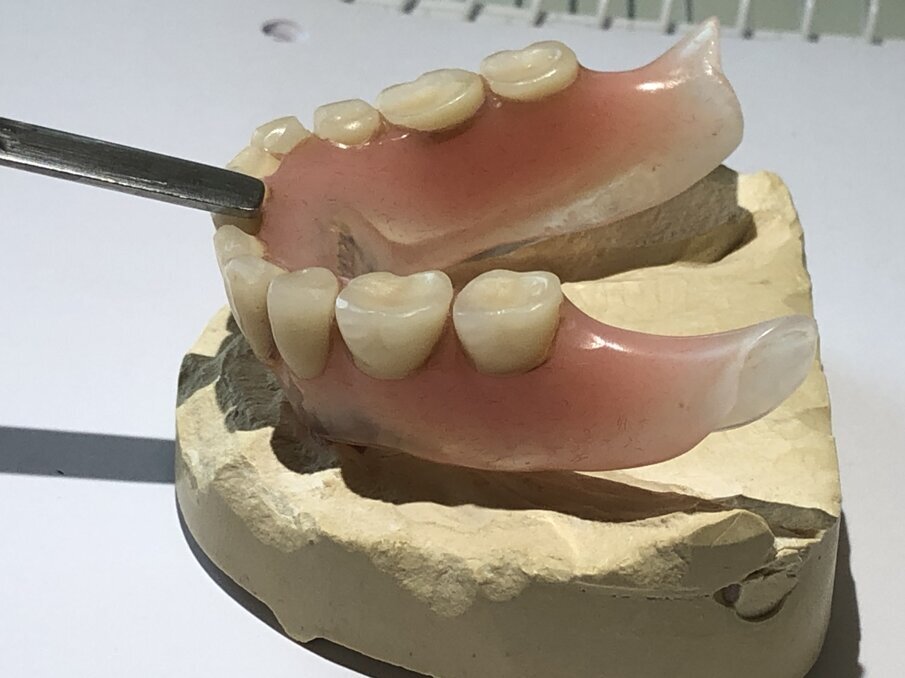

De foto’s van de dolderstaaf in deze publicatie zijn afkomstig van een patiënt, waarvan wij de constructie hebben vernieuwd wegens onvoldoende houvast. Om de dolderstaafconstructie eenvoudiger en sneller in de productie te vervaardigen, wordt vaak een nauwkeurig secundair onderdeel in de prothese achterwege gelaten. Dit betekent dat de huidige prothese zonder precisiebasis wordt geslepen en de dolderstaaf in de prothese wordt gepolymeriseerd zonder een geschikt secundair onderdeel (afbeelding 1, 2, 3, 4 en 5).

De digitale freestechnologie en CAD/CAM-technologie bestaan al enige tijd. Met deze digitale technologieën worden de staafconstructies op zowel primaire als secundaire onderdelen gefreesd met behulp van machines. Dit biedt een exacte pasvorm van het secundaire deel dat in de prothese aan de staaf is bevestigd. Bovendien zorgen twee tot drie kleine kunststofonderdelen voor een nog betere grip.

Om de staaf een goede houvast te geven en het voor patiënten eenvoudiger te maken om de prothese in en uit te nemen, wordt het secundair gefreesde metalen deel volledig met kunststof bedekt. Wij kunnen dit realiseren door in plaats van twee à drie kleine kunststof onderdelen, een volledig secundair deel in kunststof gefreesd met CAD/CAM in het secundaire metalen deel te lijmen (afbeelding 9).